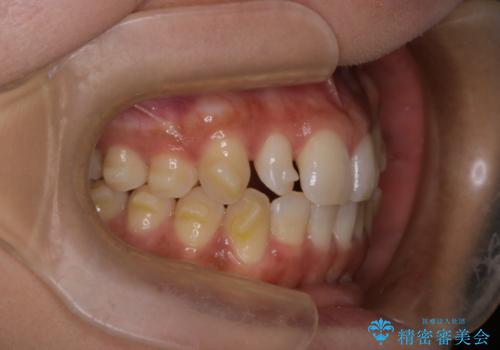

反対咬合と前歯のガタガタを非抜歯で改善

- 患者様は、上下の前歯のガタガタと反対咬合(下の歯が上の歯より前に出ている状態)を主訴として来院されました。診断の結果、抜歯を行わずに治療を進めるため、臼歯を遠心移動させてスペースを作り、IPR(インタープロキシマルリダクション)で歯間を調整する治療計画を立てました。インビザラインを使用して、透明で目立たない矯正装置により、歯列を整えながら噛み合わせも改善することを目標としました。

非抜歯での治療では、限られたスペースの中で効率的に歯を動かす必要があります。本症例では、臼歯を後方に移動させる遠心移動を行い、歯列のガタガタを改善しました。また、IPRを適切に行うことでスペースを確保し、歯根や歯肉への負担を最小限に抑えながら治療を進めました。インビザラインを使用することで、治療中も目立ちにくく、患者様の日常生活への影響を軽減しました。結果として、抜歯を行わずに美しい歯並びと自然な噛み合わせを実現し、患者様には大変満足していただけました。